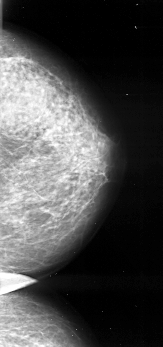

A_1026_1.LEFT_MLO

LEFT_MLO LINES 6271 PIXELS_PER_LINE 2851 BITS_PER_PIXEL 16 RESOLUTION 42 OVERLAY

FILE: A_1026_1.LEFT_MLO.OVERLAY

TOTAL_ABNORMALITIES 1

ABNORMALITY 1

LESION_TYPE CALCIFICATION TYPE PLEOMORPHIC DISTRIBUTION CLUSTERED

ASSESSMENT 4

SUBTLETY 1

PATHOLOGY MALIGNANT